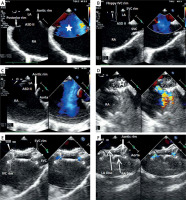

Transoesophageal echocardiography (Figure 1), performed under general anaesthesia, confirmed a large secundum atrial septal defect measuring up to 27 mm with deficient aortic rim, floppy inferior vena cava rim, and a short superior vena cava rim.

Figure 1

Transoesophageal images of device closure of a large secundum atrial septal defect with deficient superior vena cava. A – Four-chamber view (zoom); on the left side: secundum atrial septal defect in the middle part of the septum, dilated right atrium. Good visualization of the present posterior rim and deficient aortic rim; on the right side: TEE with colour Doppler showing a very large atrial septal defect with left-to-right shunt (white star). B – Bicaval view presenting a short superior vena cava rim and thin and floppy inferior vena cava rim. C – Short-axis view focused on the aortic valve showing lack of the aortic rim. D – Sizing balloon catheter inflated across the defect (empty white star) during simultaneous device deployment from the right upper pulmonary vein. E – Final result after release of the device; bicaval view with colour Doppler compare TEE showing typical device conformation with small residual leaks and unobstructed flow from the superior vena cava. F – Final result after release of the device: short-axis view with colour Doppler compare presenting the occluder well positioned on the aorta with small residual flow

SVC – superior vena cava, IVC – inferior vena cava, Ao – aortic valve, LA – left atrium, RA – right atrium, ASD II – secundum atrial septal defect.